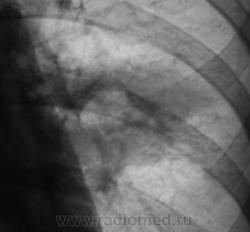

Юноша - "брат хозяйки ветки", сын, "почившего" в прошлом году. Ни в 2008, ни в 2009 на флюорограммах изменений выявлено не было.

Я намеренно, в некоторых случаях "даю" второй снимок с обработкой, дабы стали видимыми "мягкие" очаговые и другие компоненты.